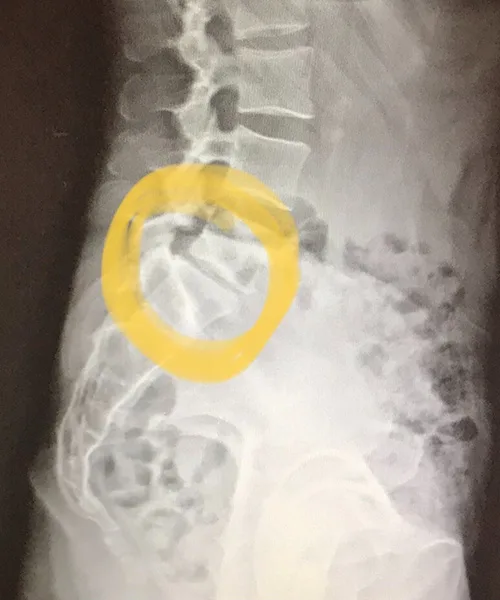

Radiographs of Sophie Coffey’s back showed disc compression and deterioration in the lower lumbar region, which potentially could limit her days in the saddle if left untreated.

It didn’t. Which is how, about a week ago, I found myself staring at an X-ray of my lower back, listening to a doctor explain about disc deterioration and the space between this and that and how my 39-year-old spine was more normally seen in people much older than me. Eventually I was able to ask the most important question: Will I be able to keep riding?